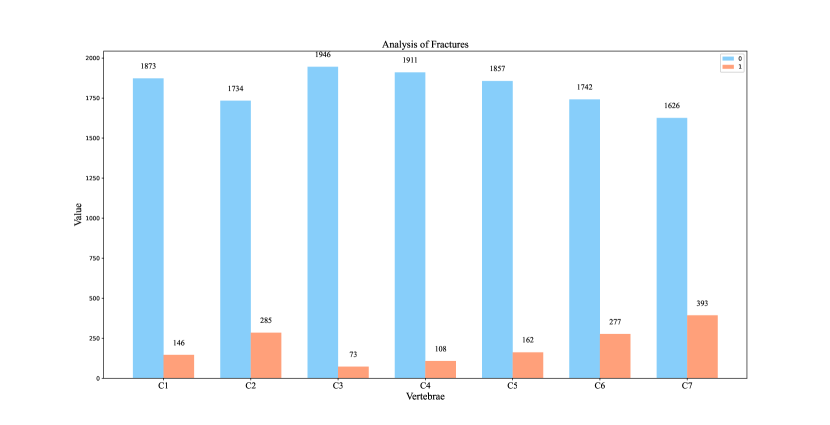

The primary dataset for this task is reasonably balanced, with a split of approximately 52% for non-fractured and 48% for fractured cases. Within the fractured cases, there is significant variability, with C7 having the highest proportion of fractures at 19%, while C3 exhibits the lowest incidence at 4%. It’s noteworthy that some patients may present with multiple fractures, which tend to occur in close proximity, such as between C4 and C5, rather than being dispersed across different vertebrae as shown in Figure 3. The medical image data is stored in Digital Imaging and Communications in Medicine (DICOM) format, a well-established standard for medical image storage. Information like image size, pixel dimensions, brightness, contrast, and pixel value range can be extracted from DICOM metadata, providing essential insights for image interpretation. Additionally, there are bounding boxes for a subset of the training data.